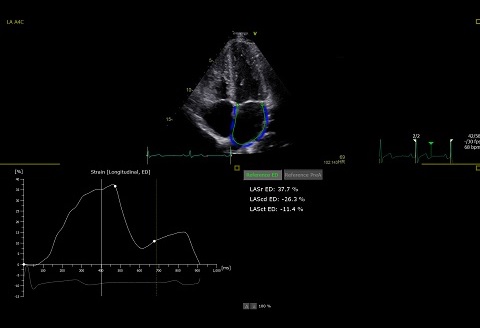

AutoStrain LA

Strain Task Forceの標準化コンセンサス・レポートに則った2Dスペックル・トラッキングを使用し、LAストレイン解析を迅速かつ簡単に評価することができます。